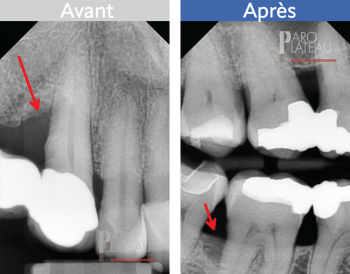

La greffe osseuse

Cette procédure consiste à corriger une déficience osseuse localisée. Cette dernière peut avoir été causée par une parodontite ou un incident local. Nous ajouterons de l’os et une membrane généralement faite de collagène pour combler ce manque.

Avant

Après